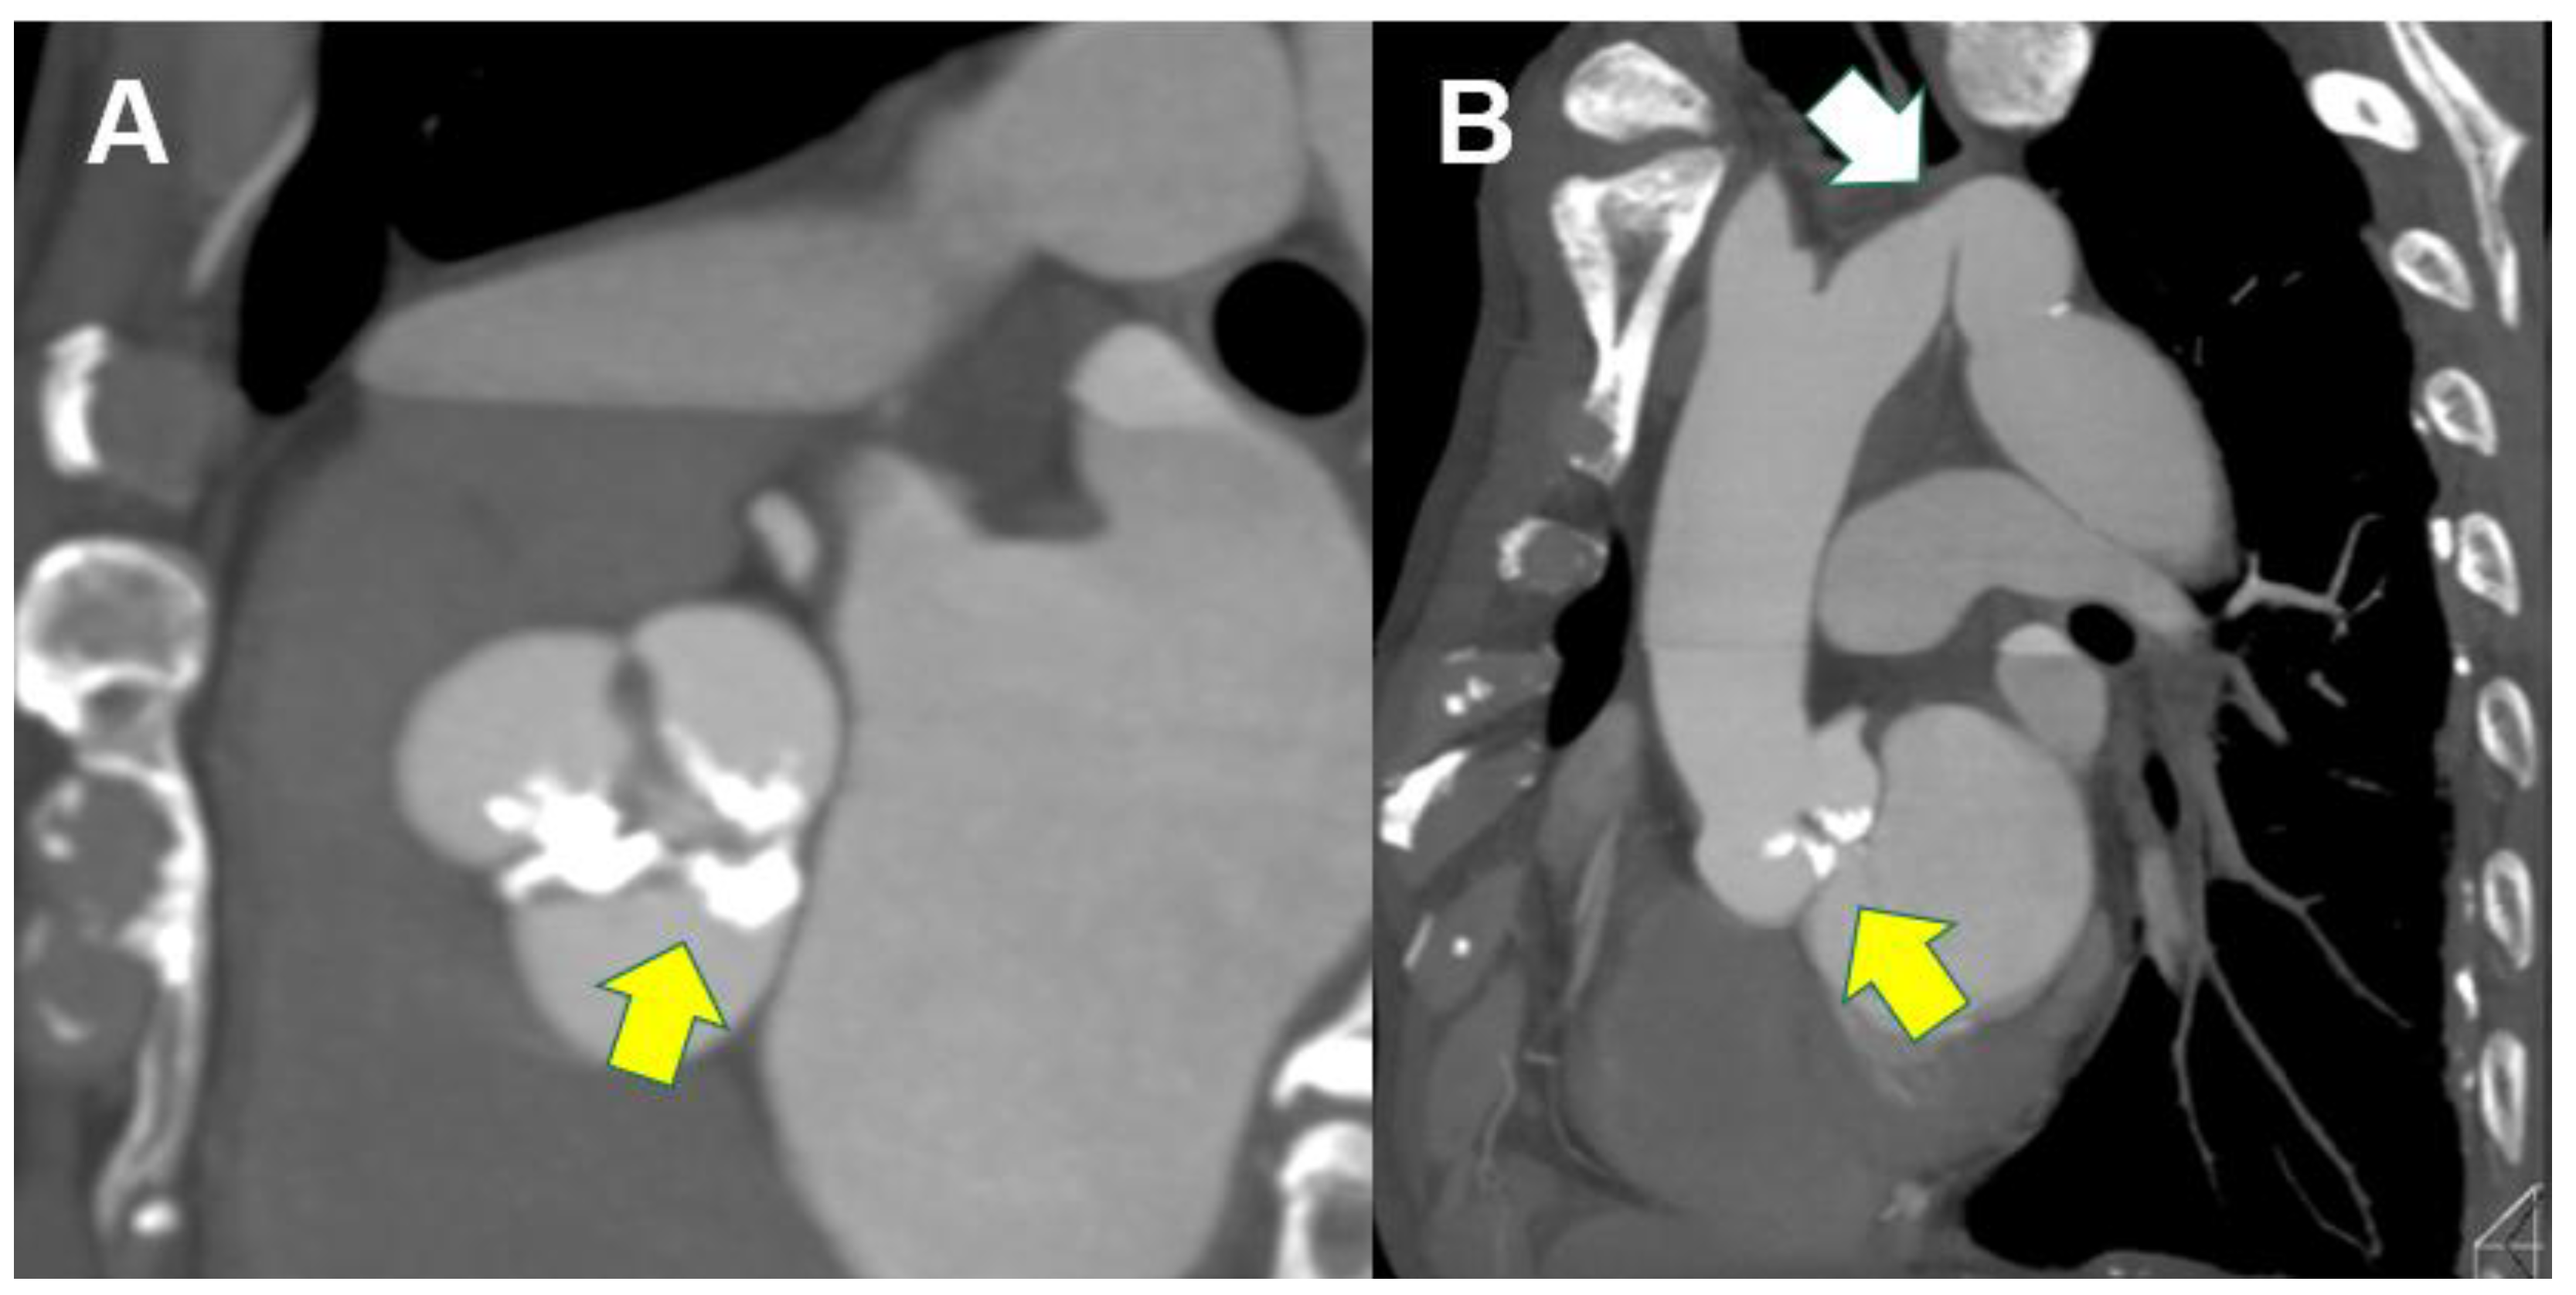

4.4. CT Analysis Before Valve-In Valve TAVI or TAV in TAV

- Blanke, P.; Soon, J.; Dvir, D.; Park, J.K.; Naoum, C.; Kueh, S.H.; Wood, D.A.; Norgaard, B.L.; Selvakumar, K.; Ye, J.; et al. Computed tomography assessment for transcatheter aortic valve in valve implantation: The vancouver approach to predict anatomical risk for coronary obstruction and other considerations. J. Cardiovasc. Comput. Tomogr. 2016, 10, 491–499. [Google Scholar] [CrossRef]

- Ribeiro, H.B.; Rodés-Cabau, J.; Blanke, P.; Leipsic, J.; Park, J.K.; Bapat, V.; Makkar, R.; Simonato, M.; Barbanti, M.; Schofer, J.; et al. Incidence, predictors, and clinical outcomes of coronary obstruction following transcatheter aortic valve replacement for degenerative bioprosthetic surgical valves: Insights from the VIVID registry. Eur. Heart J. 2018, 39, 687–695. [Google Scholar] [CrossRef]